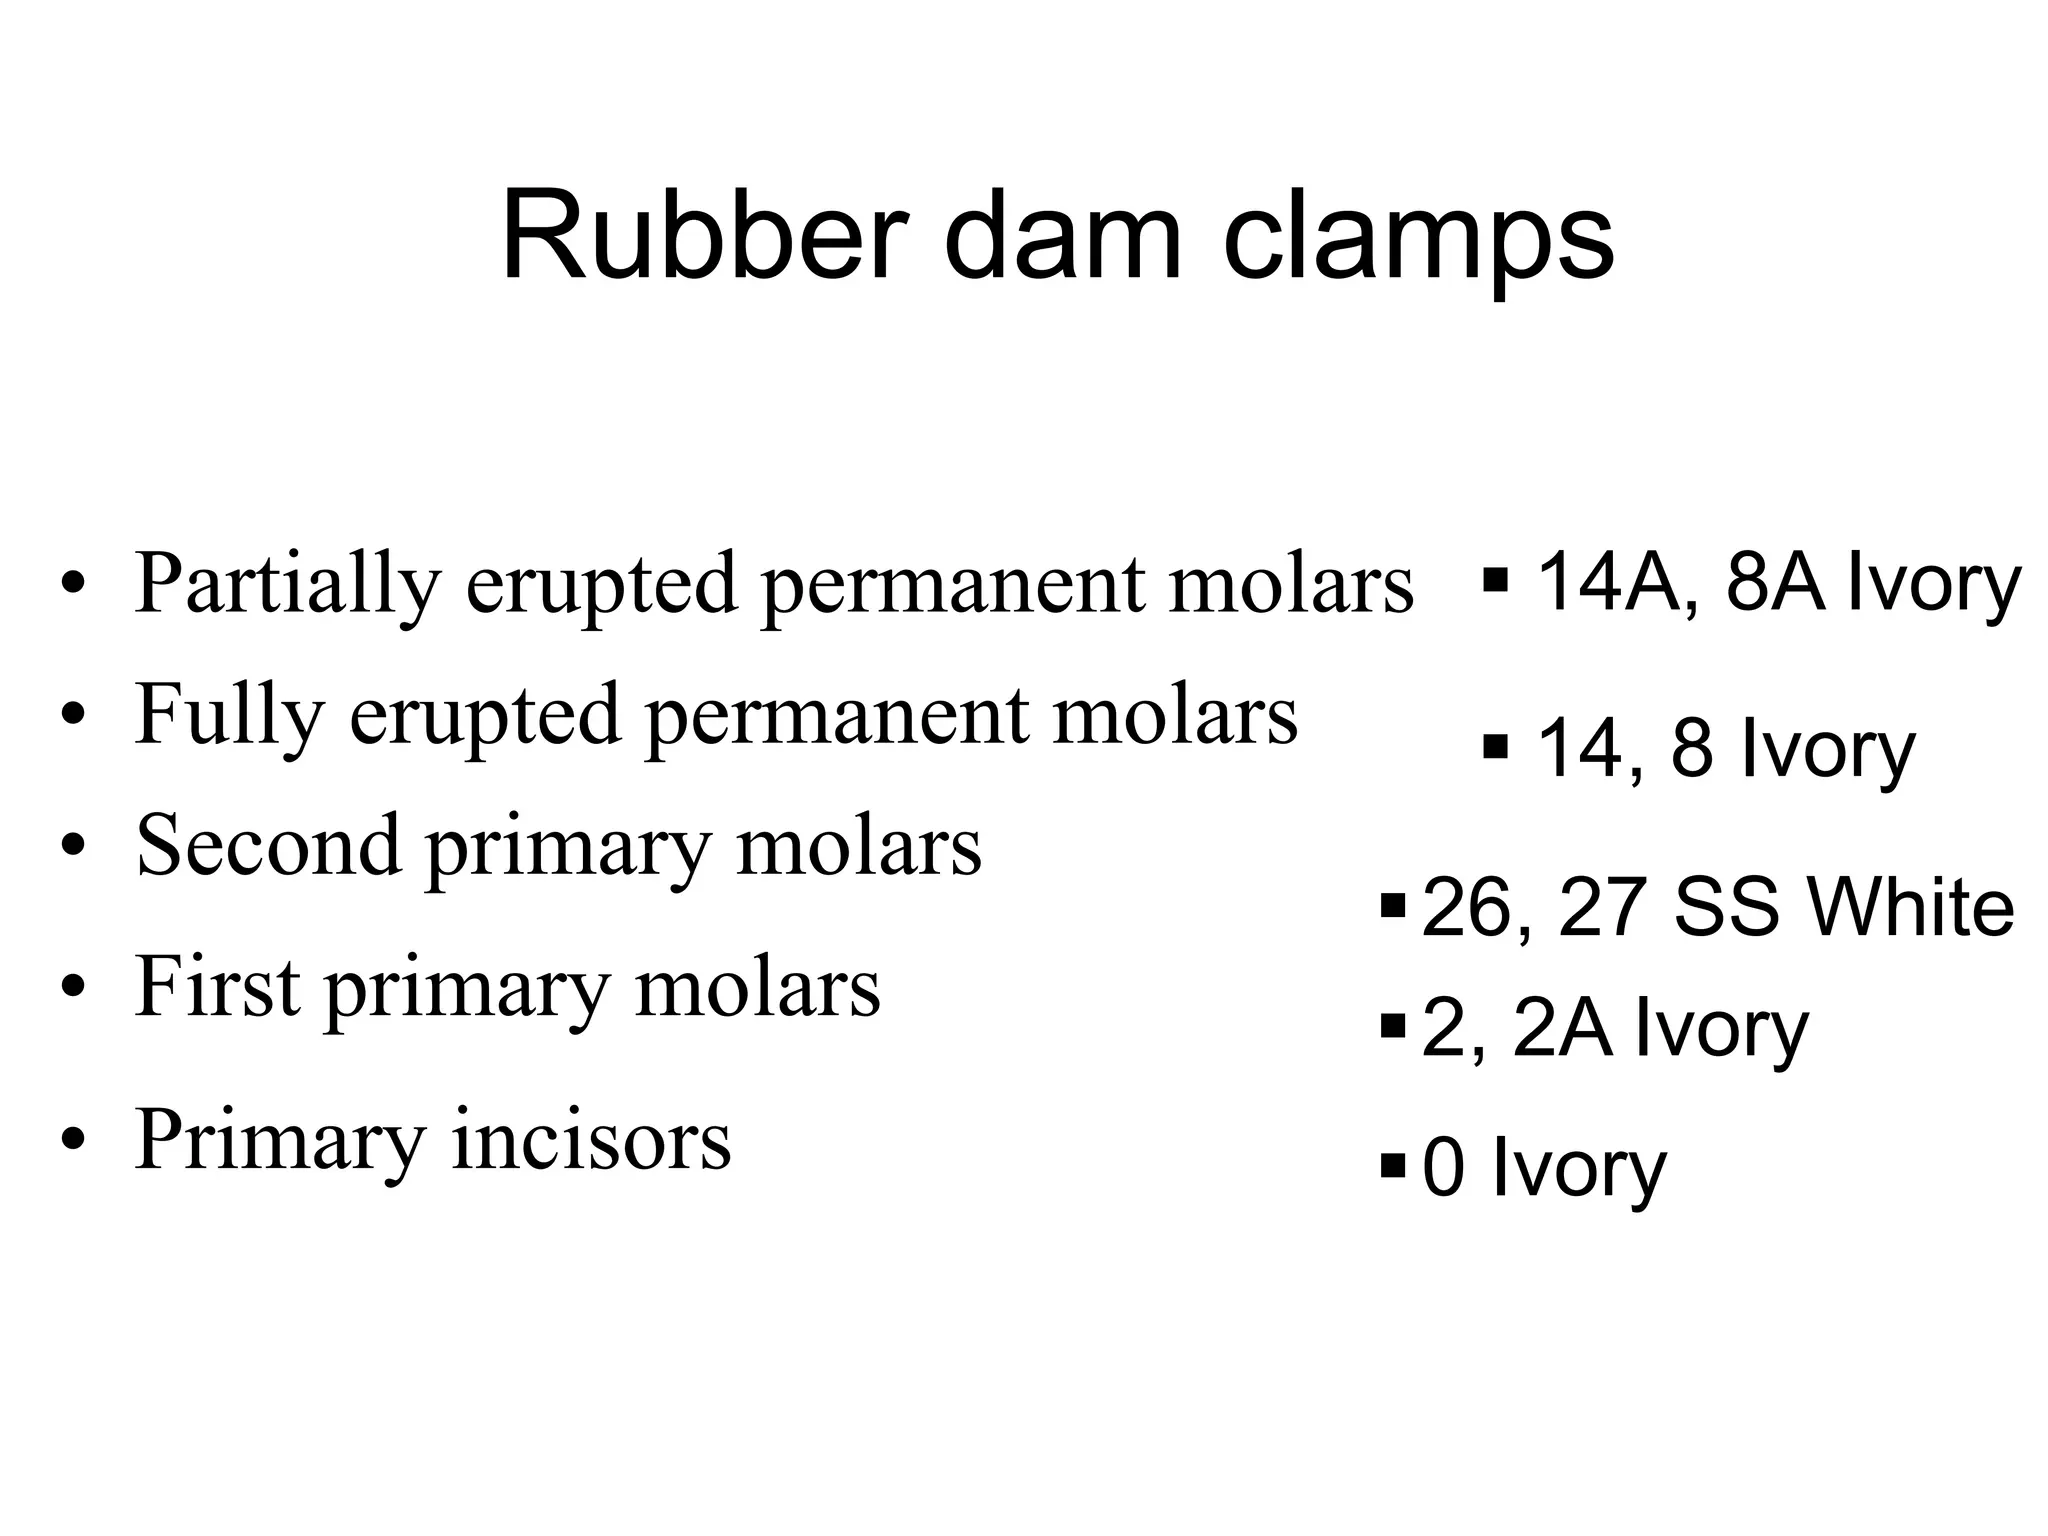

This document discusses the materials and components used for rubber dam isolation in dentistry. It describes the different types of rubber dam materials including color options and napkins to absorb moisture. It also outlines the tools needed such as punches to make holes, templates and stamps to guide hole placement, clamps to secure the dam, and other accessories like wedges and lubricant. Finally, it provides guidance on punching holes for different types of teeth and properly placing clamps in the rubber dam.